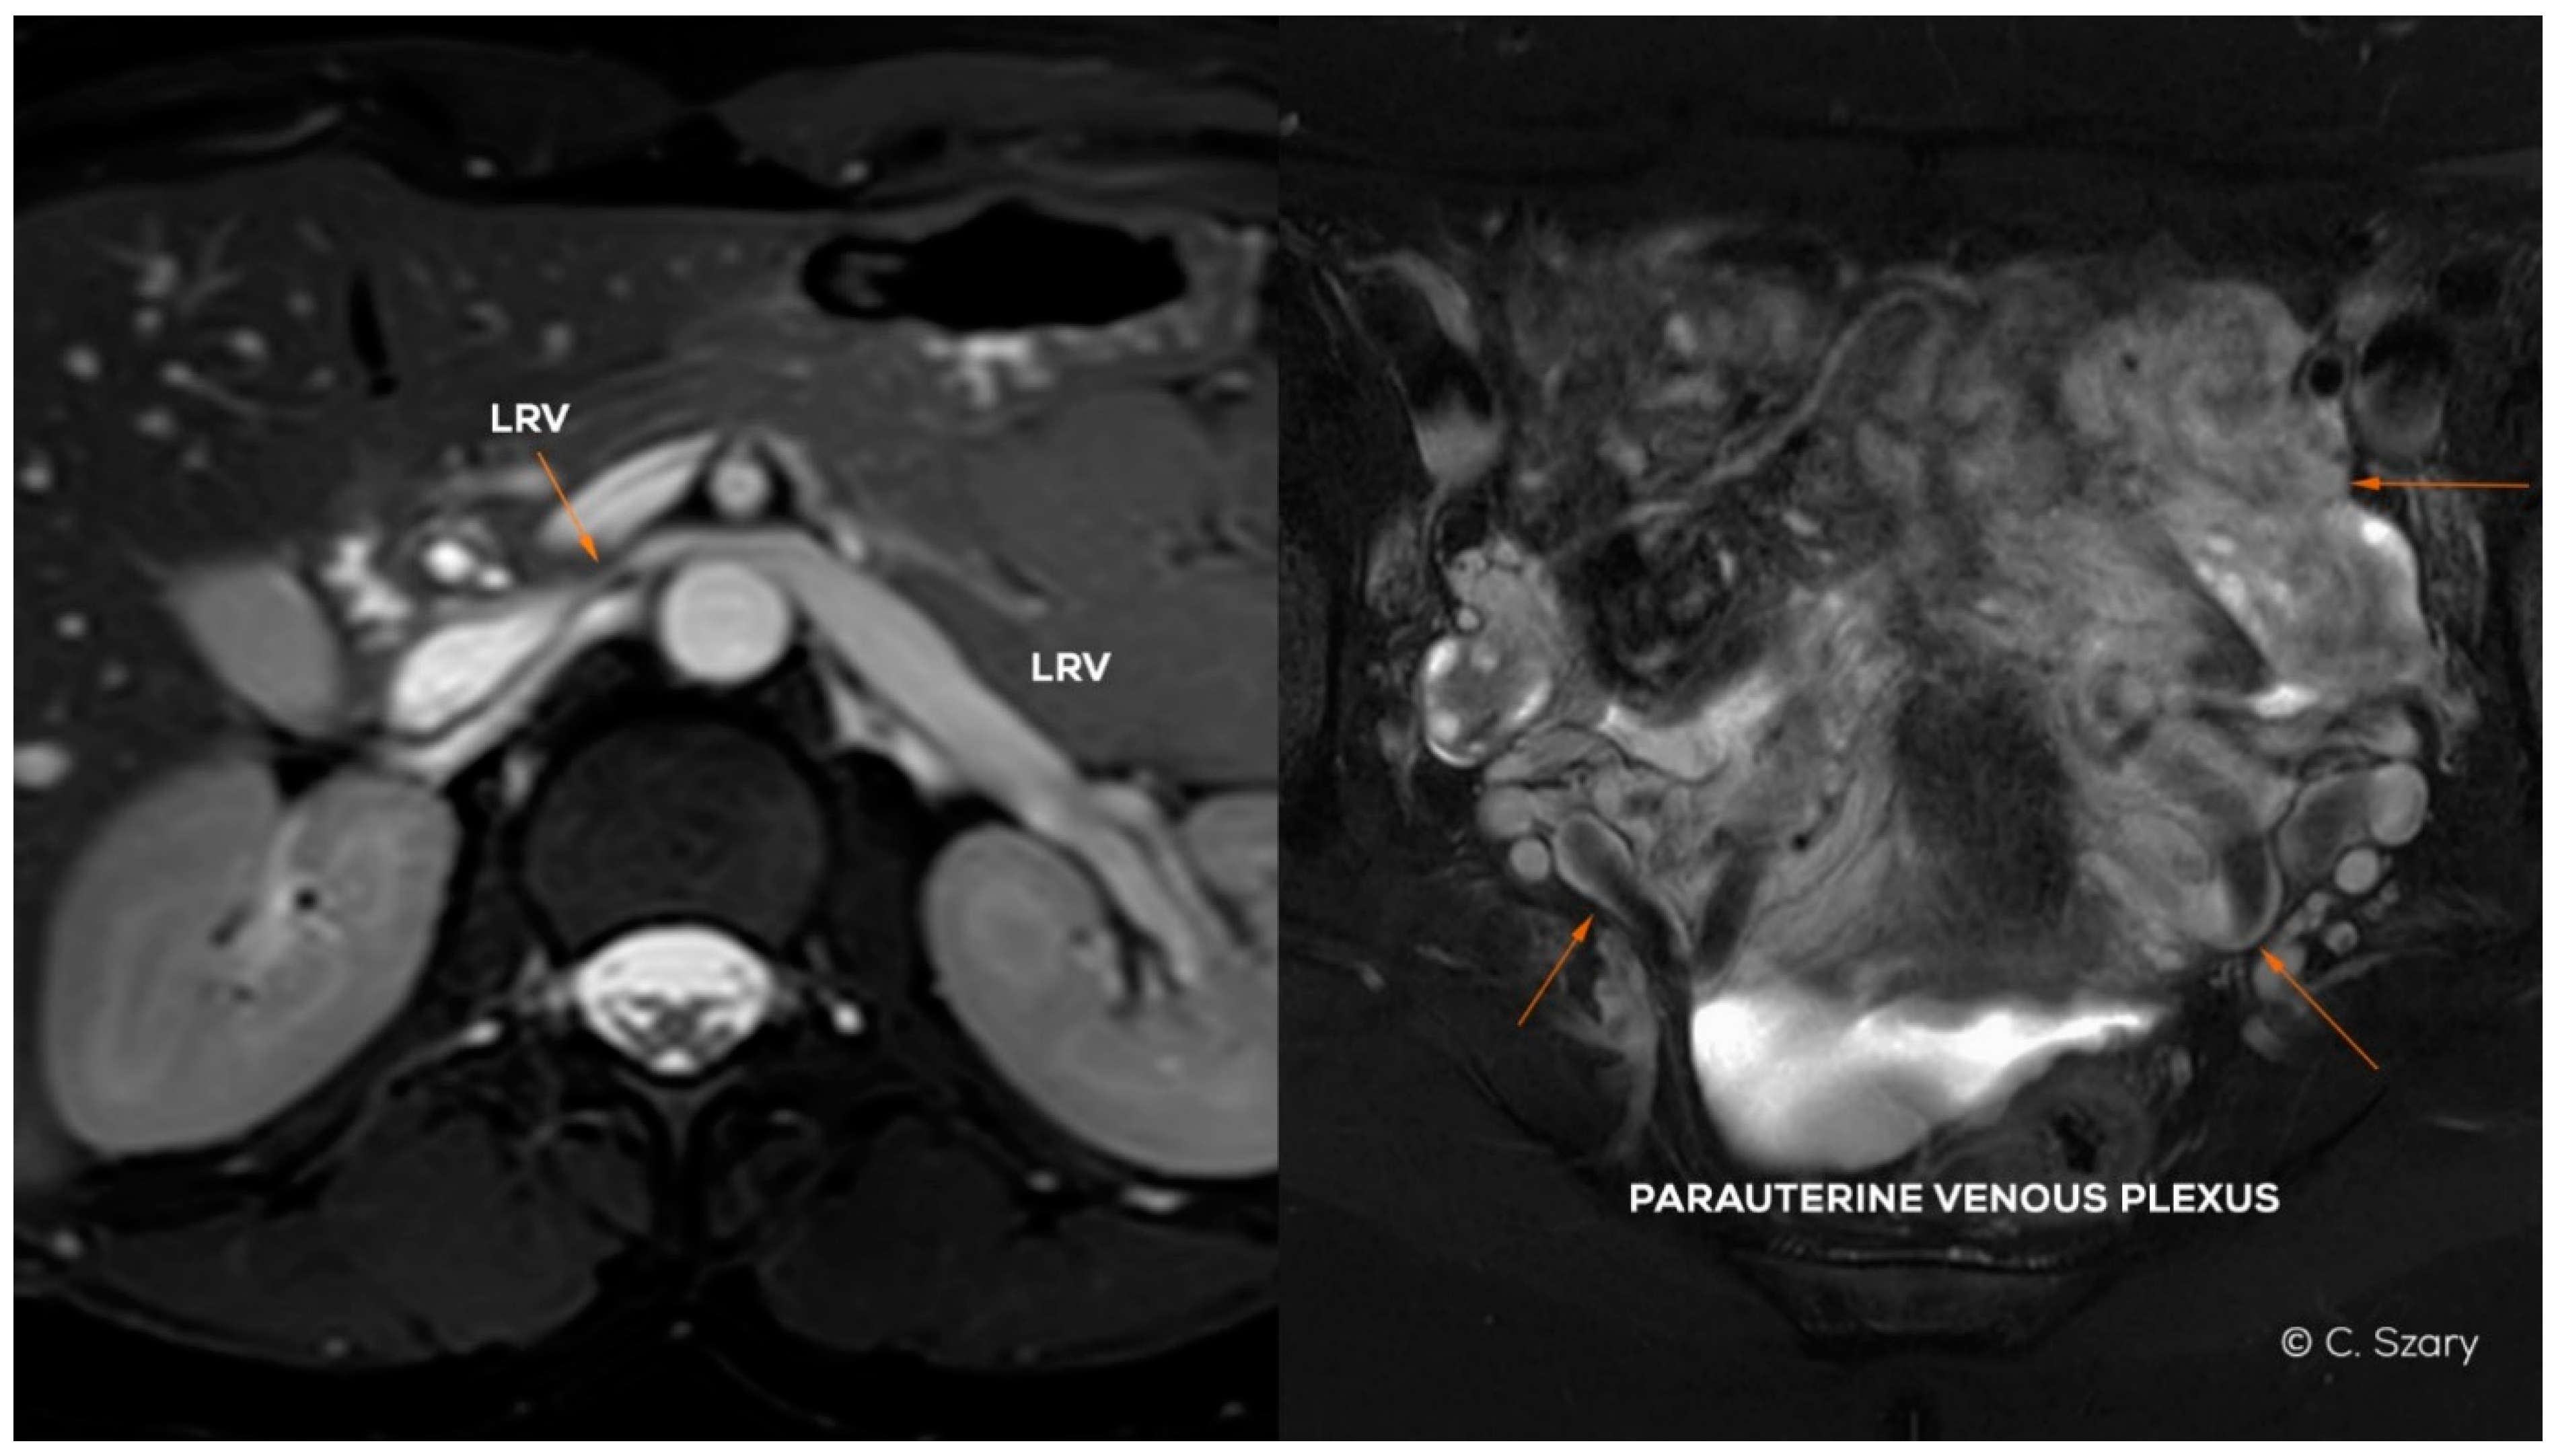

Pelvic venous insufficiency (PVI) is a very common hemodynamic phenomenon (estimated to be present in 20–43% of the population in women) [1,2,3], most often resulting from the reversal of venous blood flow, which occurs in the mechanism of outflow disorders, or excessive dilatation of the main venous axes (VAX) located within the abdomen and pelvis. The abovementioned pathophysiological phenomenon results in overloading of the capacitive venous vessels in the pelvis, most often the para-uterine and peri-vaginal venous plexuses (Figure 1), thus generating so-called venous leaks from the pelvis and vulvo-perineal varicosities.

Figure 1.

Illustration of abdominal and pelvic venous system in women.

Figure 4.

Magnetic resonance (MR) images (BTFE and T2-weighted sequences in axial plane) presenting LRV partial hypoplasia and secondary para-uterine varices caused by LOV insufficiency.